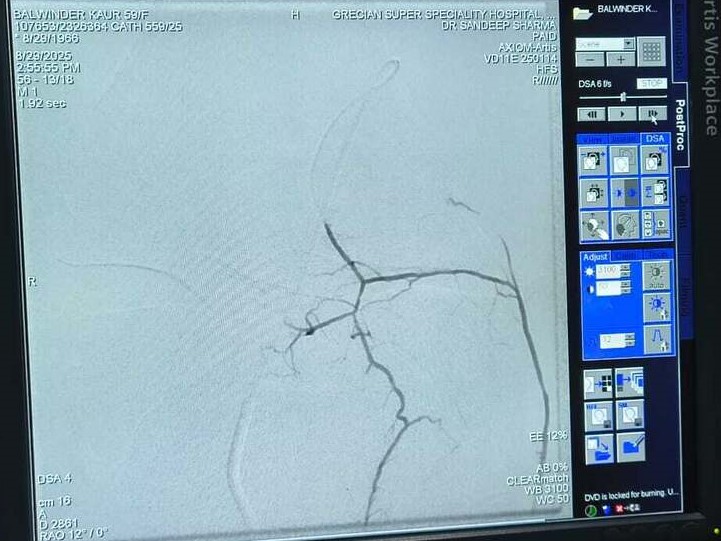

Balwinder Kaur Journey to Knee Pain Relief: A Successful GAE Treatment Story

Genicular Artery Embolization